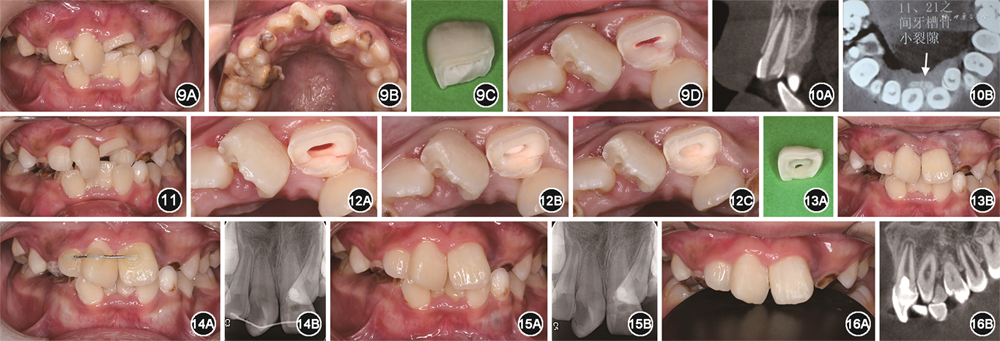

(1)一般情况:患儿男性,8岁,于2020年2月就诊于第四军医大学口腔医学院儿童口腔科,主诉上前牙外伤3 d伴疼痛不适,求治。患儿家长代述患儿外伤后无头晕恶心呕吐,既往体健,无心脑血管疾病、传染病及药物过敏史。

(2)临床检查:见图9。患儿口腔卫生差,软垢(+++)。替牙列期,牙列式:16—14,53,12—22,63,24—26,36,34,73,32—42,83—85,46。55乳牙滞留,75乳牙早失。11牙釉质-牙本质缺损,探诊(-),叩诊(+),松动Ⅰ度。21初步检查疑似为冠折露髓(图9C,冠中1/3折),松动Ⅰ度,局部清洁牙齿后可见21腭侧折断达龈下,松动Ⅱ度(图9D)。前牙区牙列拥挤,22个别牙反

,软组织及颞下颌关节未见明显异常。

(3)影像学检查:见图10。锥形束CT显示11、21牙根发育至Nolla 9期,21复杂冠根折,腭侧折裂线平牙槽嵴顶,11、21之间可见牙槽骨小裂隙。

(1)洁治:21局部浸润麻醉,12—22于超声下清洁牙面(图11)。

(2)21牙髓切断:开髓,揭髓室顶,深度达根方髓腔折裂线下约3 mm,去除全部冠髓和部分根髓(图12A),生物陶瓷材料(IRBPP 4610 U5,Innovative Bioceramix Inc,加拿大)盖髓(图12B),玻璃离子水门汀(GC,日本)垫底(图12C)。

(3)断冠粘接:待垫底玻璃离子水门汀凝固后预备固位洞形(图13A),酸蚀,涂布粘接剂,流动树脂(7032A2,3M,美国)粘接断冠(图13B)。

(4)松牙固定:12—21弹性松牙固定(图14A),下颌

垫抬高咬合,术后根尖片显示切髓深度位于牙槽嵴顶下约3 mm(图14B)。

(5)术后1个月复诊:拆除固定,打磨抛光(图15A),根尖片显示根尖未见明显异常(图15B)。

(6)术后1年复诊:口腔检查可见牙体完整,牙龈及牙周组织健康(图16A),锥形束CT显示牙根继续发育,切髓处可见少量牙本质桥形成(图16B)。